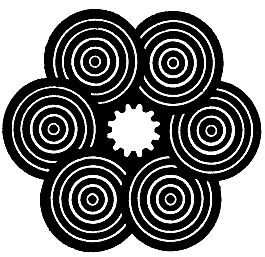

Глаза, совершенно свободные от этого недостатка, у людей встречаются редко, в чем легко можно убедиться, рассматривая приведенные здесь рис. 7, 8 и 9.

Рис. 7. Концентрические, близкие друг к другу окружности кажутся, прерванными, не одинаково удаленными друг от друга.

Рис. 8. Одинаковая (однотонная) штриховка квадрантов этого круга кажется не одинаково яркой.

Рис. 9. Те или иные буквы кажутся более темными в зависимости от положения рисунка относительно глаза.

Для испытания глаз на астигматизм врачи-окулисты часто применяют специальную таблицу (рис. 10), где двенадцать кружков имеют штриховку равной толщины через одинаковые интервалы.

Рис. 10. Фигура для определения степени и меры астигматизма глаза.

Глаз, обладающий астигматизмом, увидит линии одного или нескольких кружков более черными. Направление этих более черных линий позволяет сделать вывод о характере астигматизма глаза.